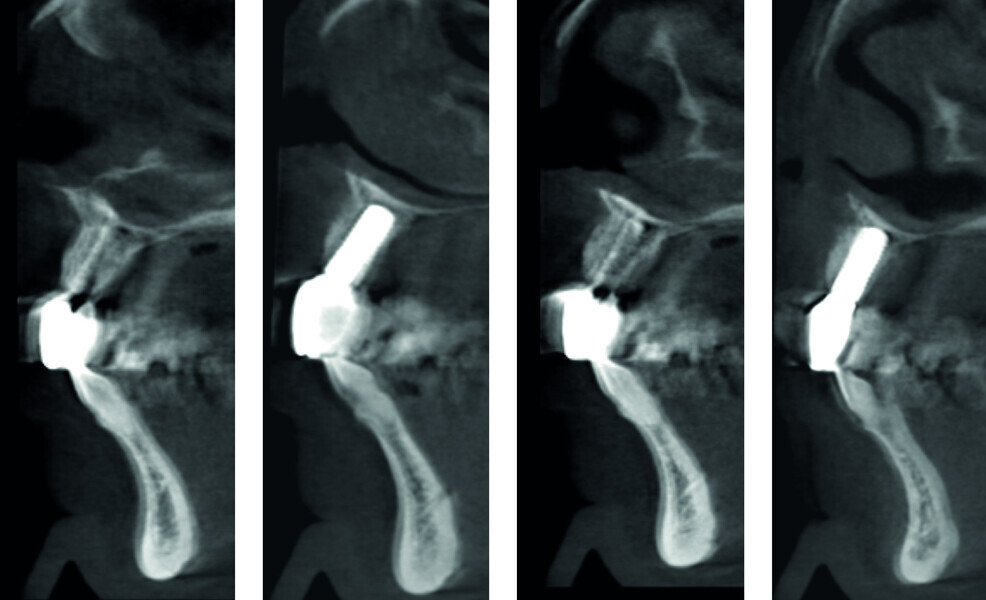

Fig. 4: Pre-op CT analysis.